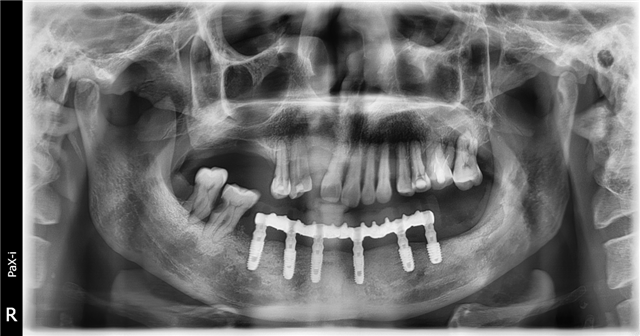

患者来到德伦口腔,接待他的是德伦口腔东风总院种植科罗朝阳副主任。经过罗主任对患者全身状态评估,口内状况及影像数据的检查,告知患者符合再种植条件,并给出了多种种植修复方案,患者知情同意,选择数字化导板种植,埋入愈合,3个月后二期修复,咬合重建,金塑桥过度,最终钛支架和烤瓷牙固定种植义齿修复方案,帮助患者恢复口腔功能及身体健康。